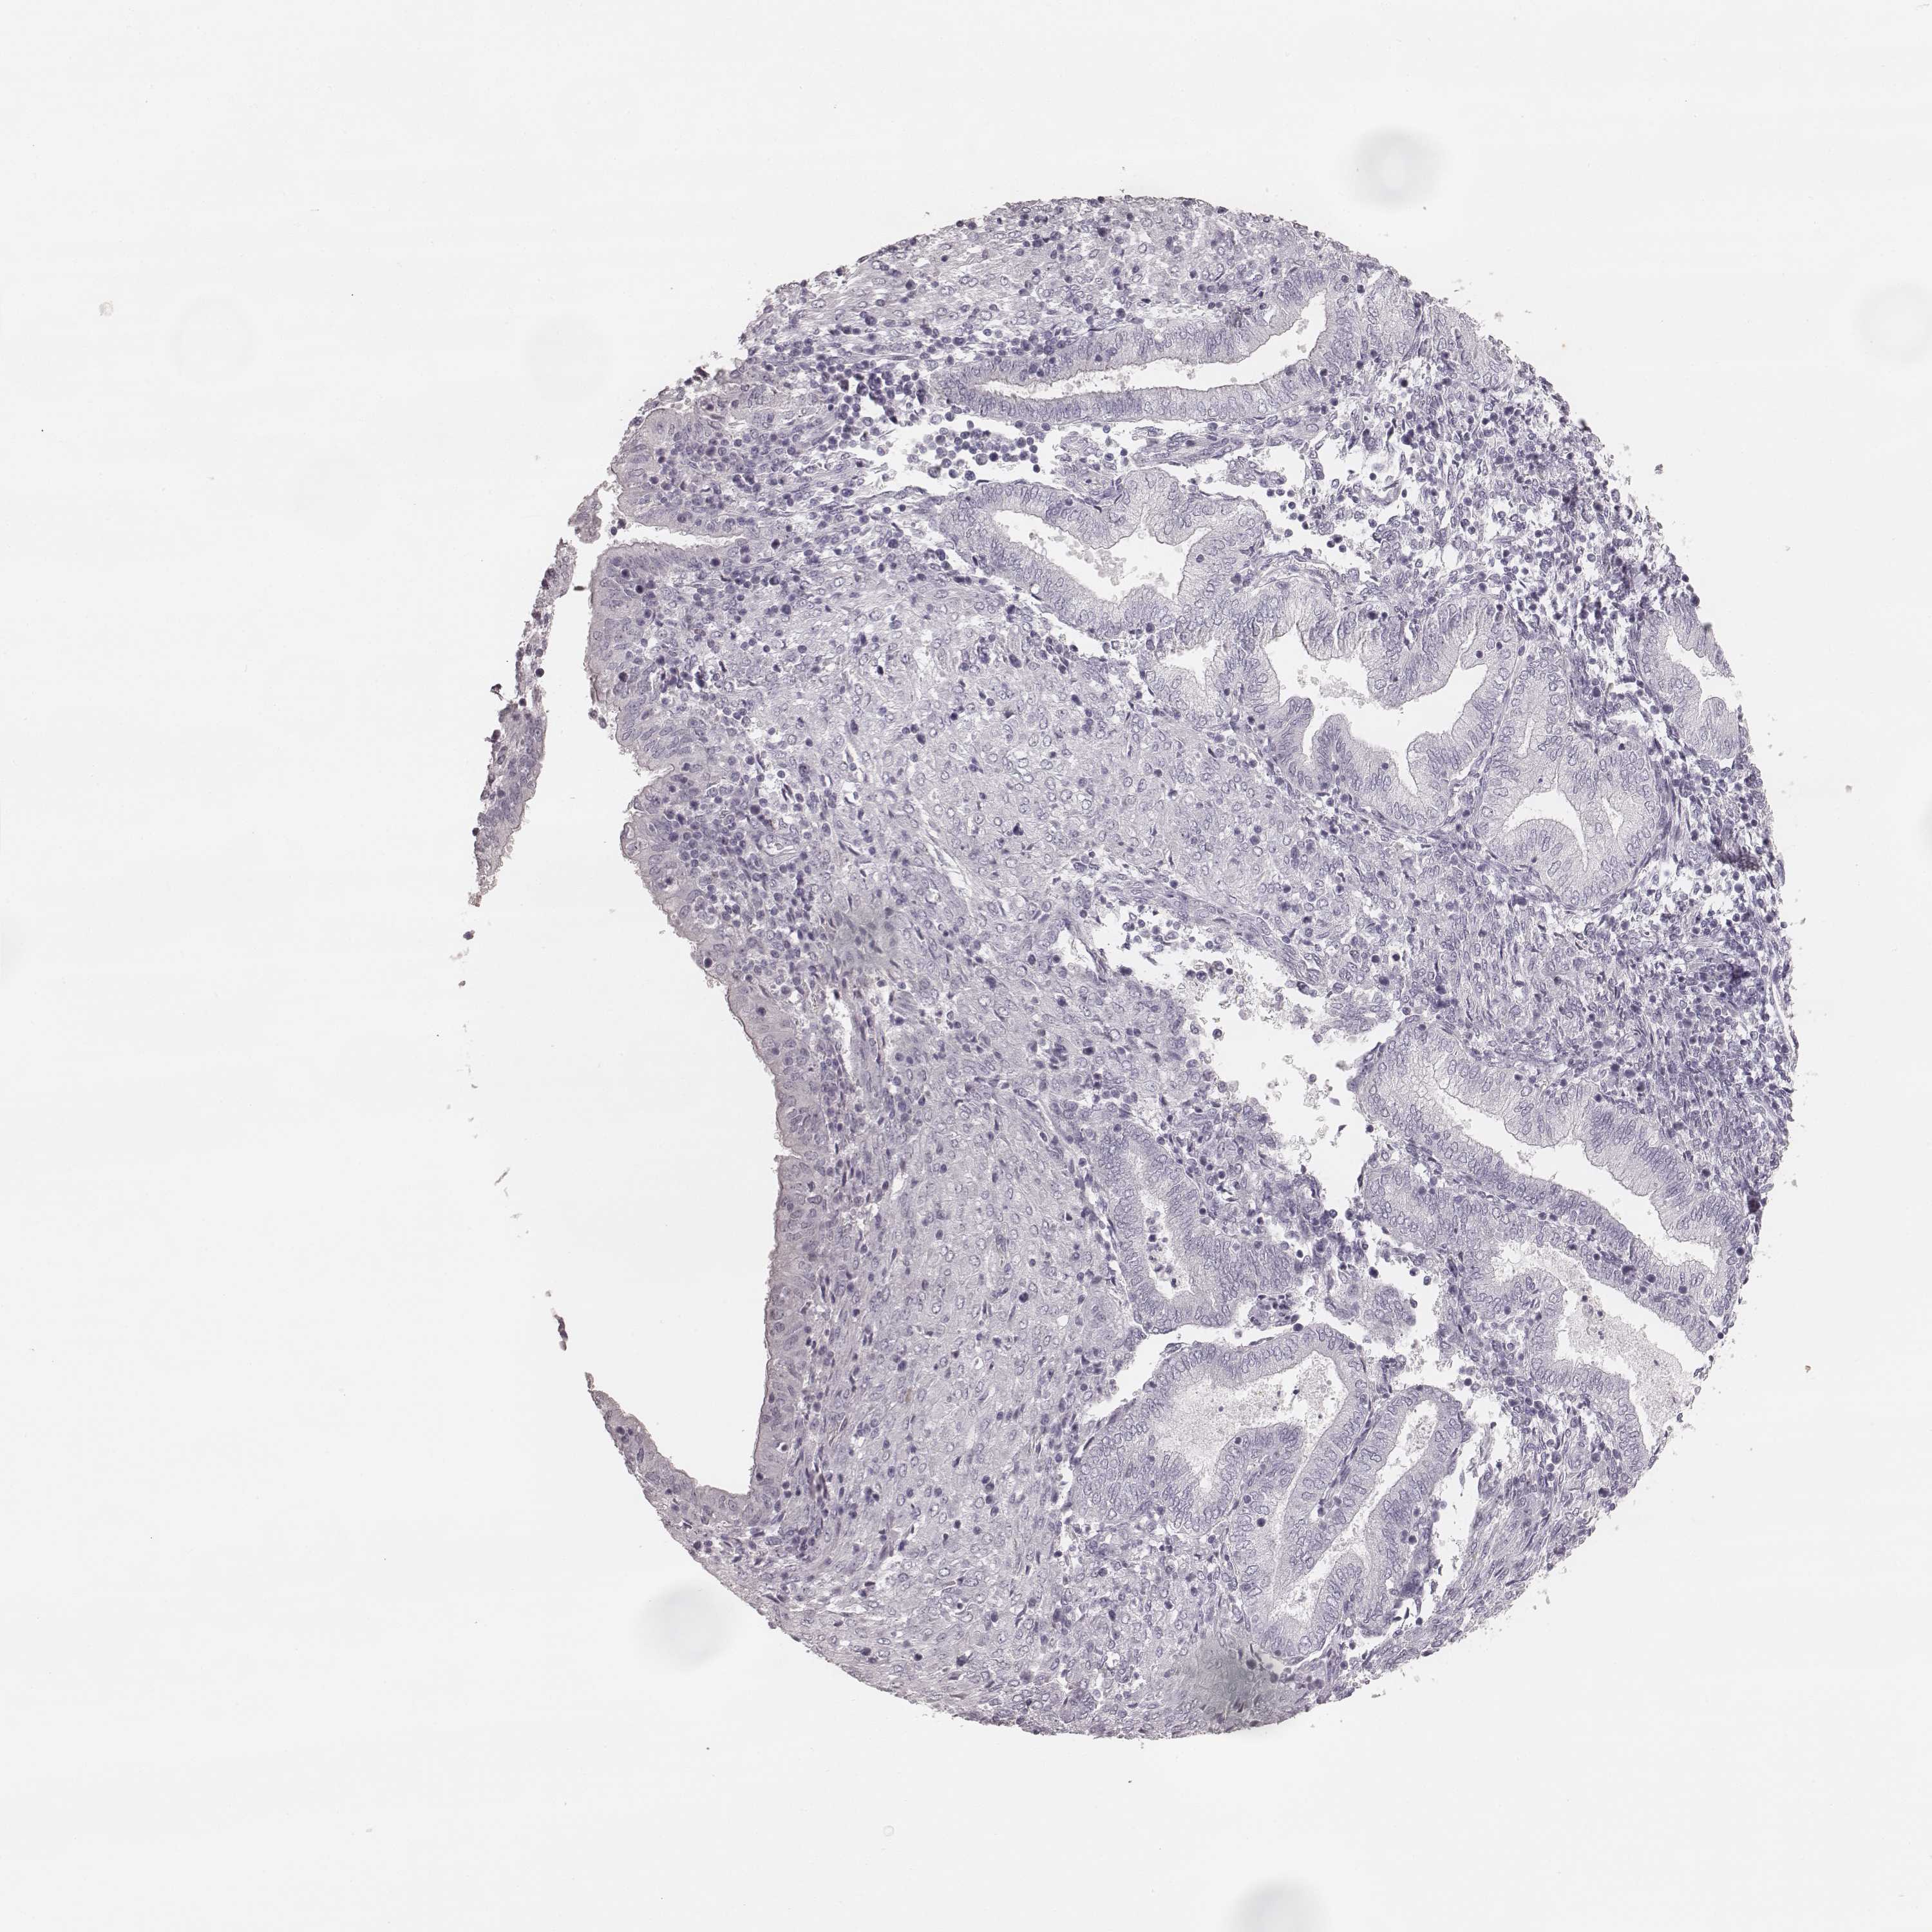

KRT82